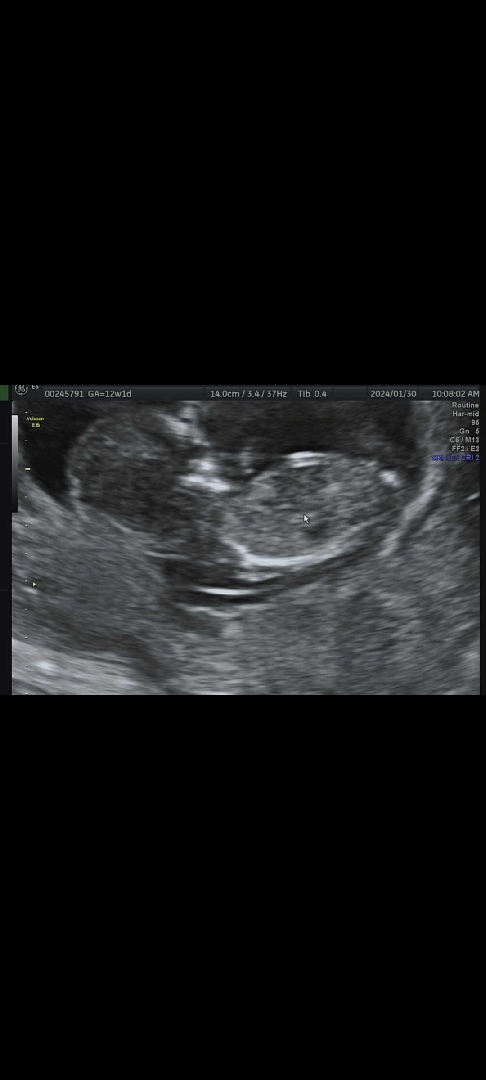

12주 각도법 고수님들 ㅠㅠ 한번 봐주세요!

12주1일인데 성별예측 너무 궁금해요 ㅠㅠ 각도법 성별 부탁드려요!